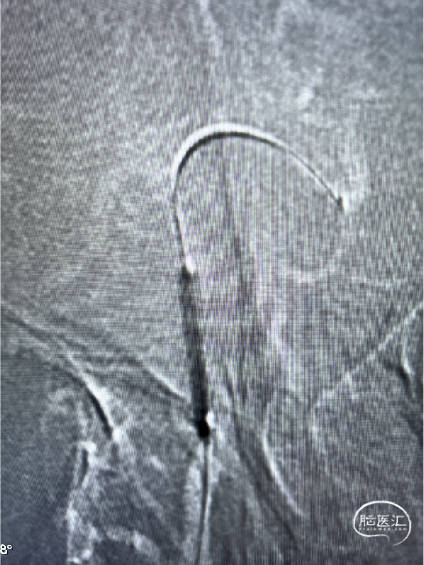

基底动脉支架置入术

术前DSA:基底动脉重度狭窄

术中球囊预扩 2.0mmX15mm

球扩后即刻DSA:狭窄明显改善

置入EZ支架3.5mmX15mm

基底动脉支架置入术后DSA:基底动脉狭窄解除,灌注明显改善,6F长鞘未损伤椎动脉。